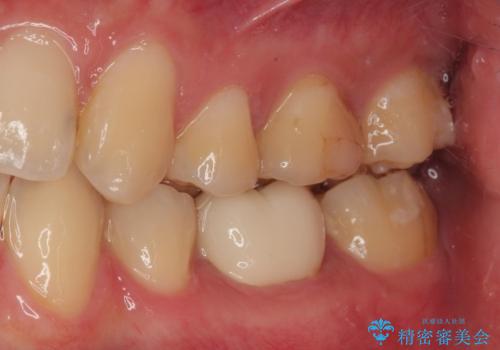

- 当院で矯正治療を終えて、左下が虫歯になっている気がするとのことで来院された患者様です。レントゲン検査の結果、コンポジットレジンによる修復箇所が複数行われており、詰め物の下に虫歯を認めました。

拡大鏡視野下でコンポジットレジン、虫歯の除去を行い、オールセラミッククラウンに適した形に整えました。